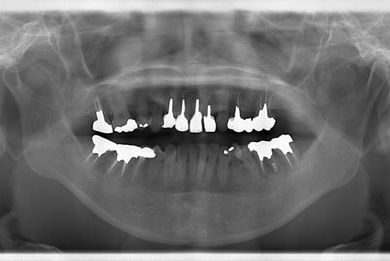

| 性別/年齢 | 女性 / 38歳 | ||||||||||||||||||||||||||||||||

| 主訴 | 奥歯の痛み(虫歯)。銀歯の所だと思います。なるべく痛くない治療がいいです。 | ||||||||||||||||||||||||||||||||

| 治療方針 | セラミック治療にて、審美的回復を行う。 | ||||||||||||||||||||||||||||||||

| 治療内容 | ハイブリッドセラミッククラウン1本(ハイブリッドセラミック用土台1本) | ||||||||||||||||||||||||||||||||

| 総治療費 | 96,600円 | ||||||||||||||||||||||||||||||||

| 治療期間 | 2ヶ月 |